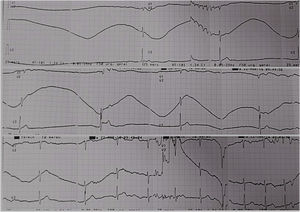

At the emergency department, she had syncope episodes associated with an asystole period lasting more than six seconds with low escape beats (Figure 1), and hypotension. Between these episodes, she was in sinus rhythm with no abnormalities in electrocardiogram (ECG) (Figure 2). Her medication history was unremarkable for negative chronotropic drugs. Due to severe sinus bradycardia and asystole during the pain episodes, a temporary transvenous pacemaker was placed to prevent syncope.

The dose was up-titrated to 600 mg daily and she was asymptomatic at discharge. At one-year follow-up, the patient remained asymptomatic, without pain episodes or syncope. Pacemaker interrogation revealed pacing rates <1% (Figure 3).